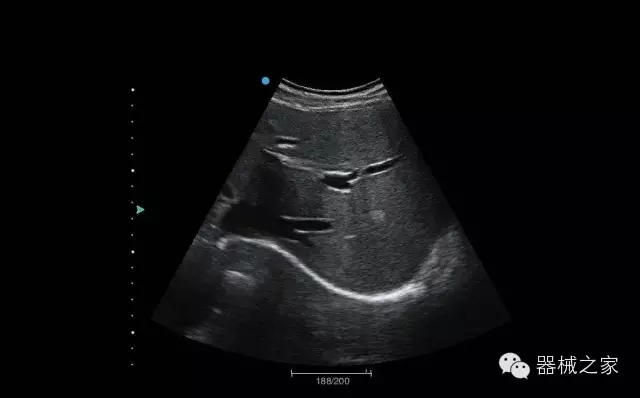

臨床圖片賞析

結甲

腎臟血流

肝血管瘤